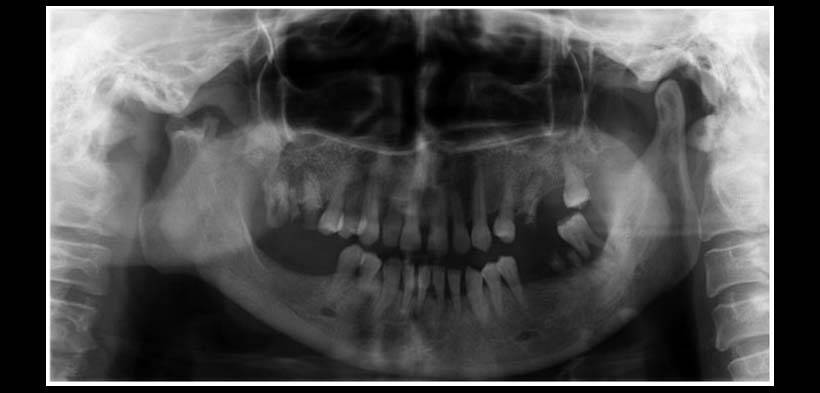

Fig. 2. Radiografía Panorámica que muestra una hipoplasia del cóndilo mandibular del lado derecho, mas alteración morfológica del cóndilo, se decide ampliar el estudio con una tomografía cone beam.